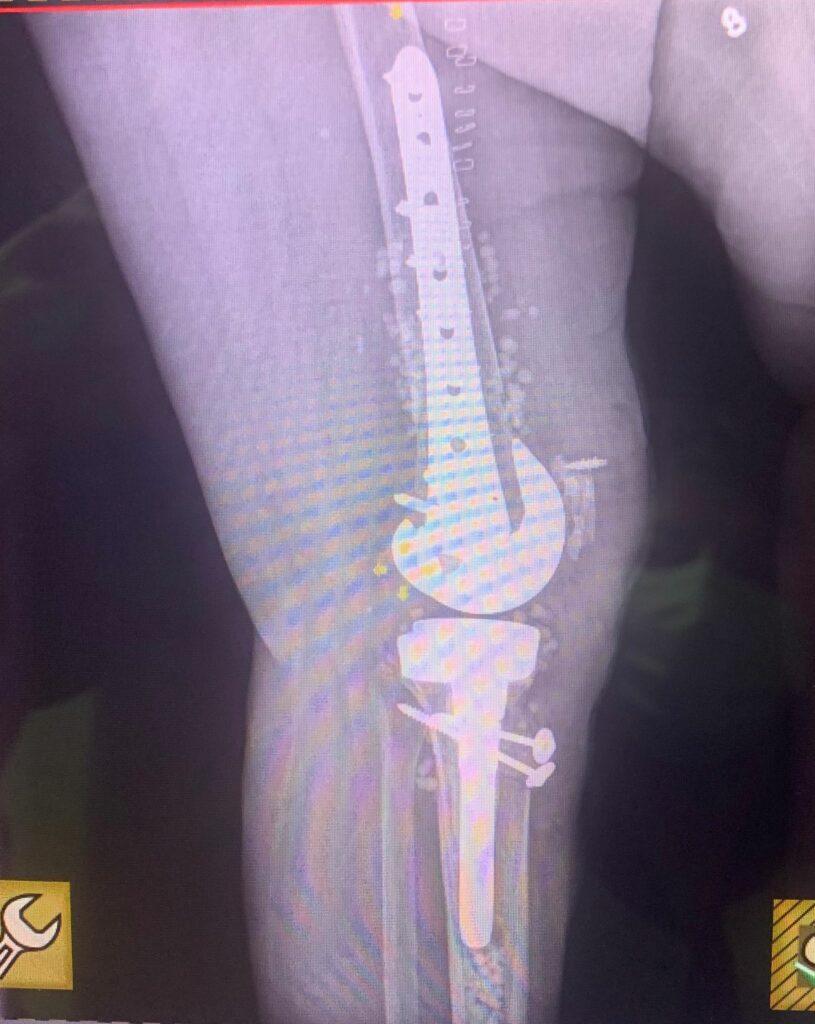

Programul de Transplant de Țesut a fost reluat la Spitalul Clinic Județean de Urgență Craiova. Clinica de Ortopedie este responsabilă de intervenții chirurgicale de transplant de tesut. Potrivit unui comunicat de presă, în data de 23 septembrie a acestui an, la o pacientă în vârstă de 73 de ani, purtătoare a patru proteze de genunchi, s-a înlocuit tendonul rotulian cu allogrefa calcaneo – ahiliană din Banca Națională de Țesut, respectând toate condițiile de securitate impuse de Normele Europene. Astfel, pacienta și-a recăpătat mobilitatea pierdută în articulația genunchiului operat.